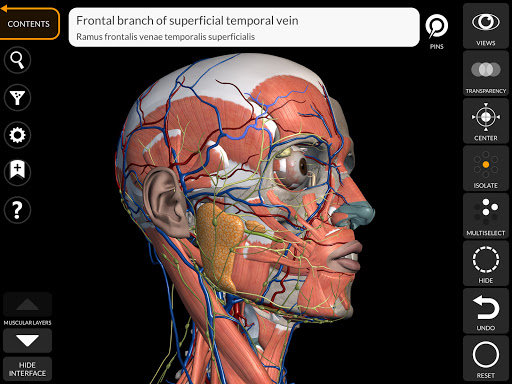

"Anatomy 3D Atlas" cho phép bạn nghiên cứu giải phẫu người theo cách dễ dàng và tương tác.

Thông qua giao diện đơn giản và trực quan, bạn có thể quan sát mọi cấu trúc giải phẫu từ mọi góc độ.

Các mô hình giải phẫu 3D đặc biệt chi tiết và có kết cấu lên đến độ phân giải 4k.

Việc phân chia theo vùng và chế độ xem được xác định trước giúp quan sát và nghiên cứu các bộ phận hoặc nhóm hệ thống riêng lẻ và mối quan hệ giữa các cơ quan khác nhau.

• Hình dung các cơ qua các lớp từ lớp nông đến lớp sâu nhất

• Bằng cách chọn một mô hình hoặc một ghim, thuật ngữ giải phẫu liên quan sẽ hiển thị

• Mô tả các cơ: nguồn gốc, chèn, chi phối thần kinh và hành động